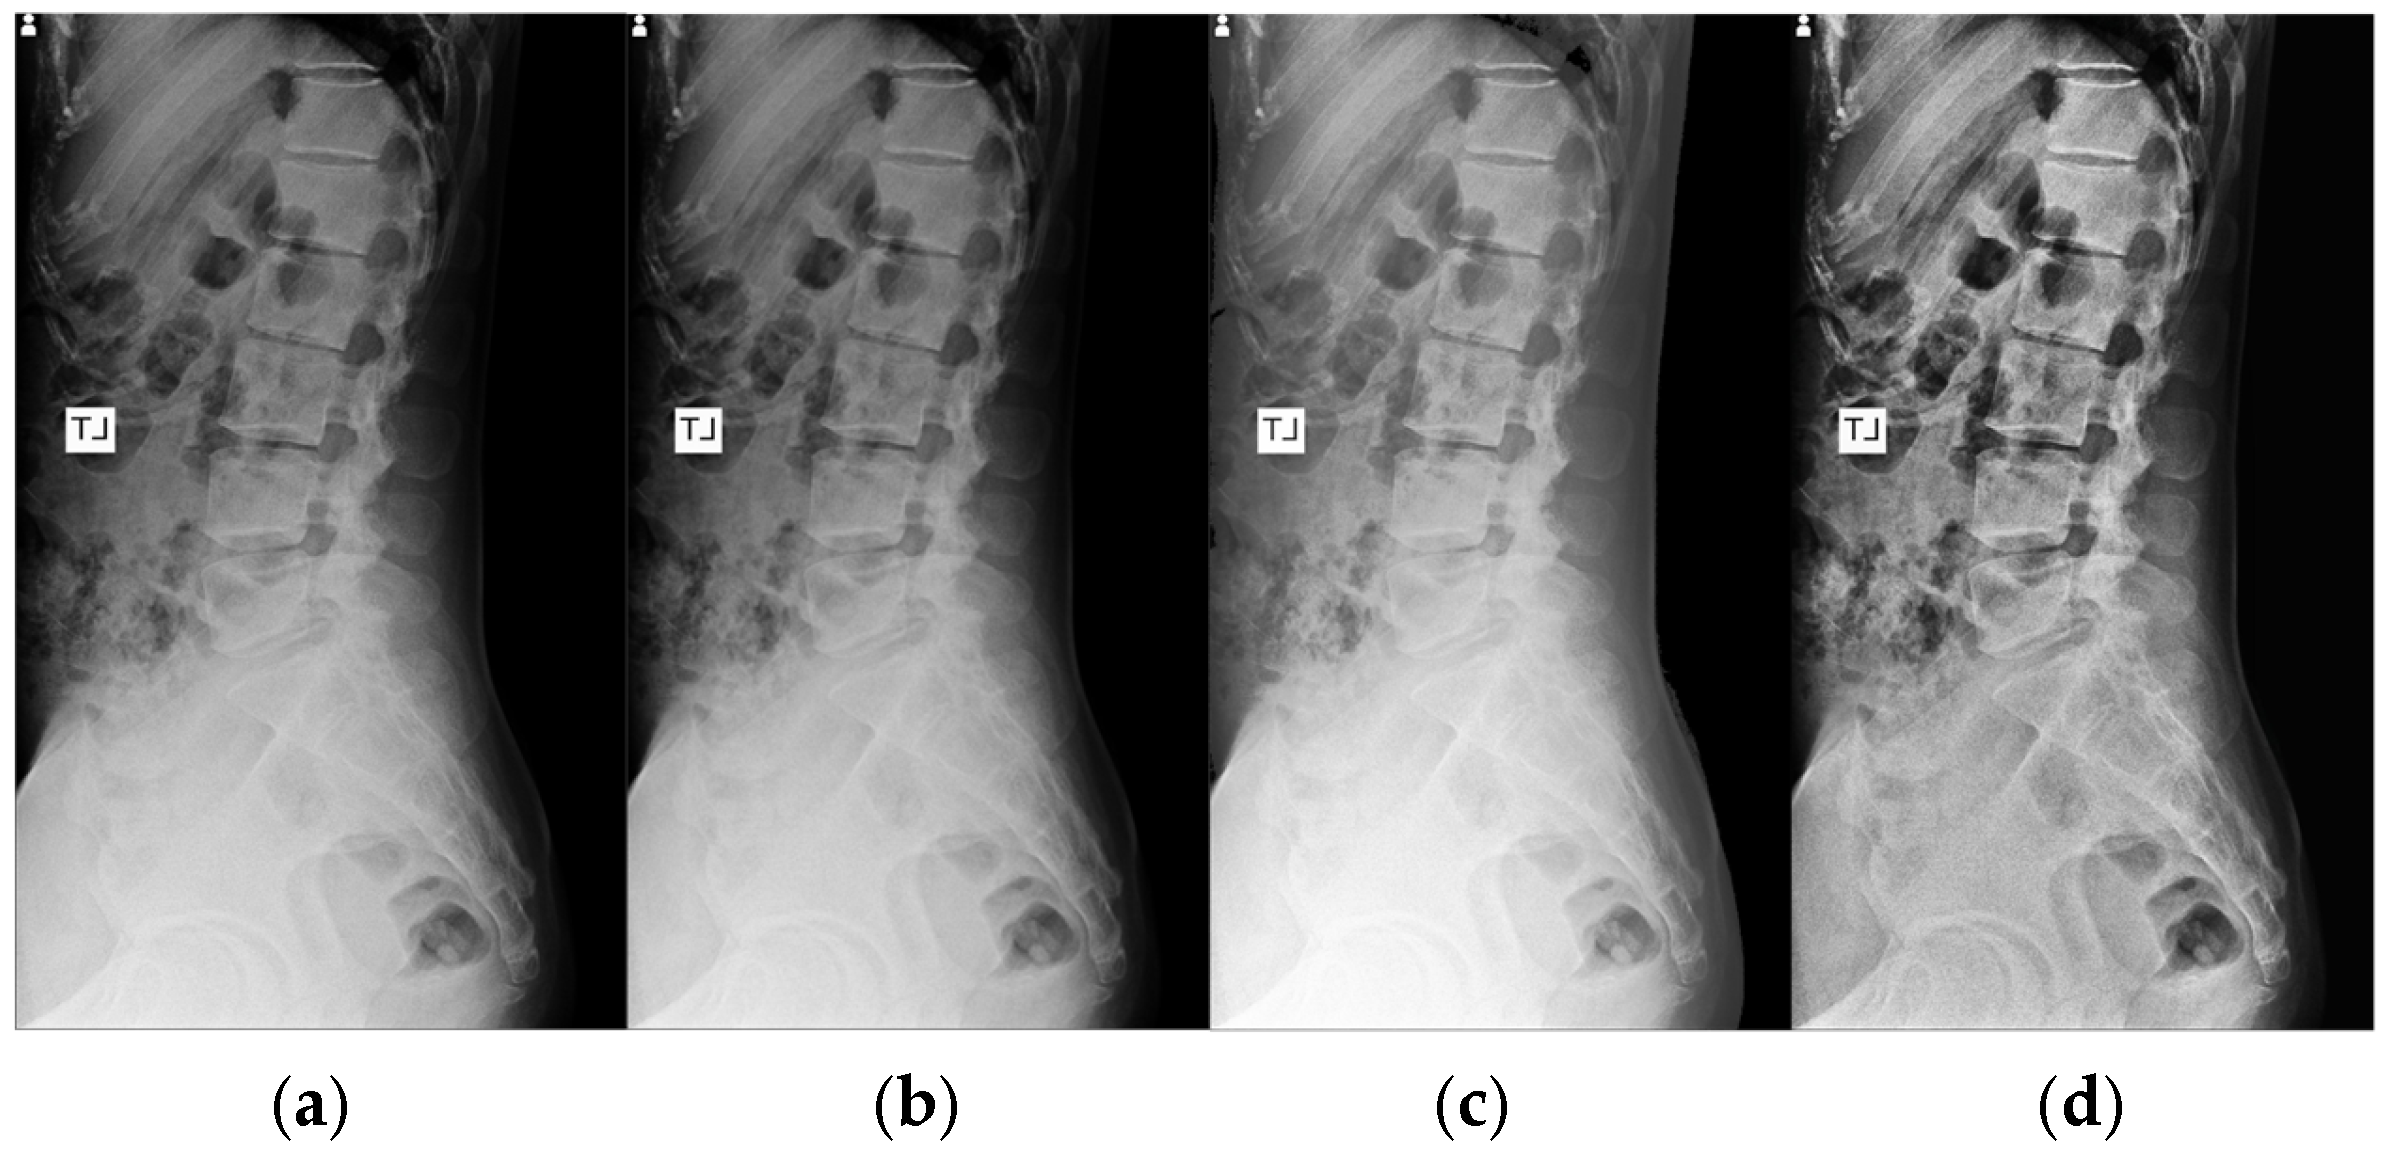

A representative image from the test dataset is selected to evaluate the model’s robustness under challenging conditions, characterized by low contrast and grain noise. As displayed in

Figure 11, the segmentation prediction is visualized for each spine segment using different colors. All the Mask R-CNN configurations successfully locate and segment the lower lumbar region (L3, L4, and L5). The application of enhancement methods notably improved performance in the upper lumbar region (L1 and L2). All models using enhanced images correctly predicted L2, and all contrast-enhancement techniques, CLAHE and HE, led to the models successfully segmenting L1. A distinct advantage of TL is observed with AD, where the TL Mask R-CNN correctly identified L1, while the scratch model failed to localize this segment.

Without enhancement, the Mask R-CNN struggles to differentiate the upper vertebrae (L1 and L2). Scratch Mask R-CNN displaying overlapping segmentation errors on the L2 spine segment. Even though the unenhanced TL model correctly labeled the actual L2, it produces a duplicate prediction, mistakenly labeling the L1 as L2. Due to this error, the model misidentified T12 (the lowest thoracic vertebra) as L1.

In contrast, the U-Net segmentation result exhibited significantly inferior performance to Mask R-CNN. Even though U-Net configurations successfully segment the L5, the models failed to consistently segment the remaining vertebrae. For L4, there exists a small area of overlap with neighboring spine segments for AD, CLAHE, and HE. In HE, the model struggles to produce the L4 segment, with L5 prediction overlaps. For upper vertebrae (L1, L2, and L3), the U-Net managed only partial and fragmented predictions.